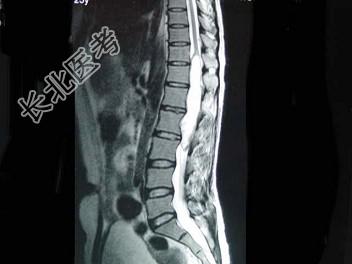

- 单项选择题男,43岁, 背部疼痛,双下肢瘫痪, 查体:下腹部以下深浅感觉障碍, 提睾反射消失,结合图像, 最可能的诊断是 ( )

A、星形细胞瘤

B、脑膜瘤

C、神经鞘膜瘤

D、神经纤维瘤

E、髓内室管膜瘤